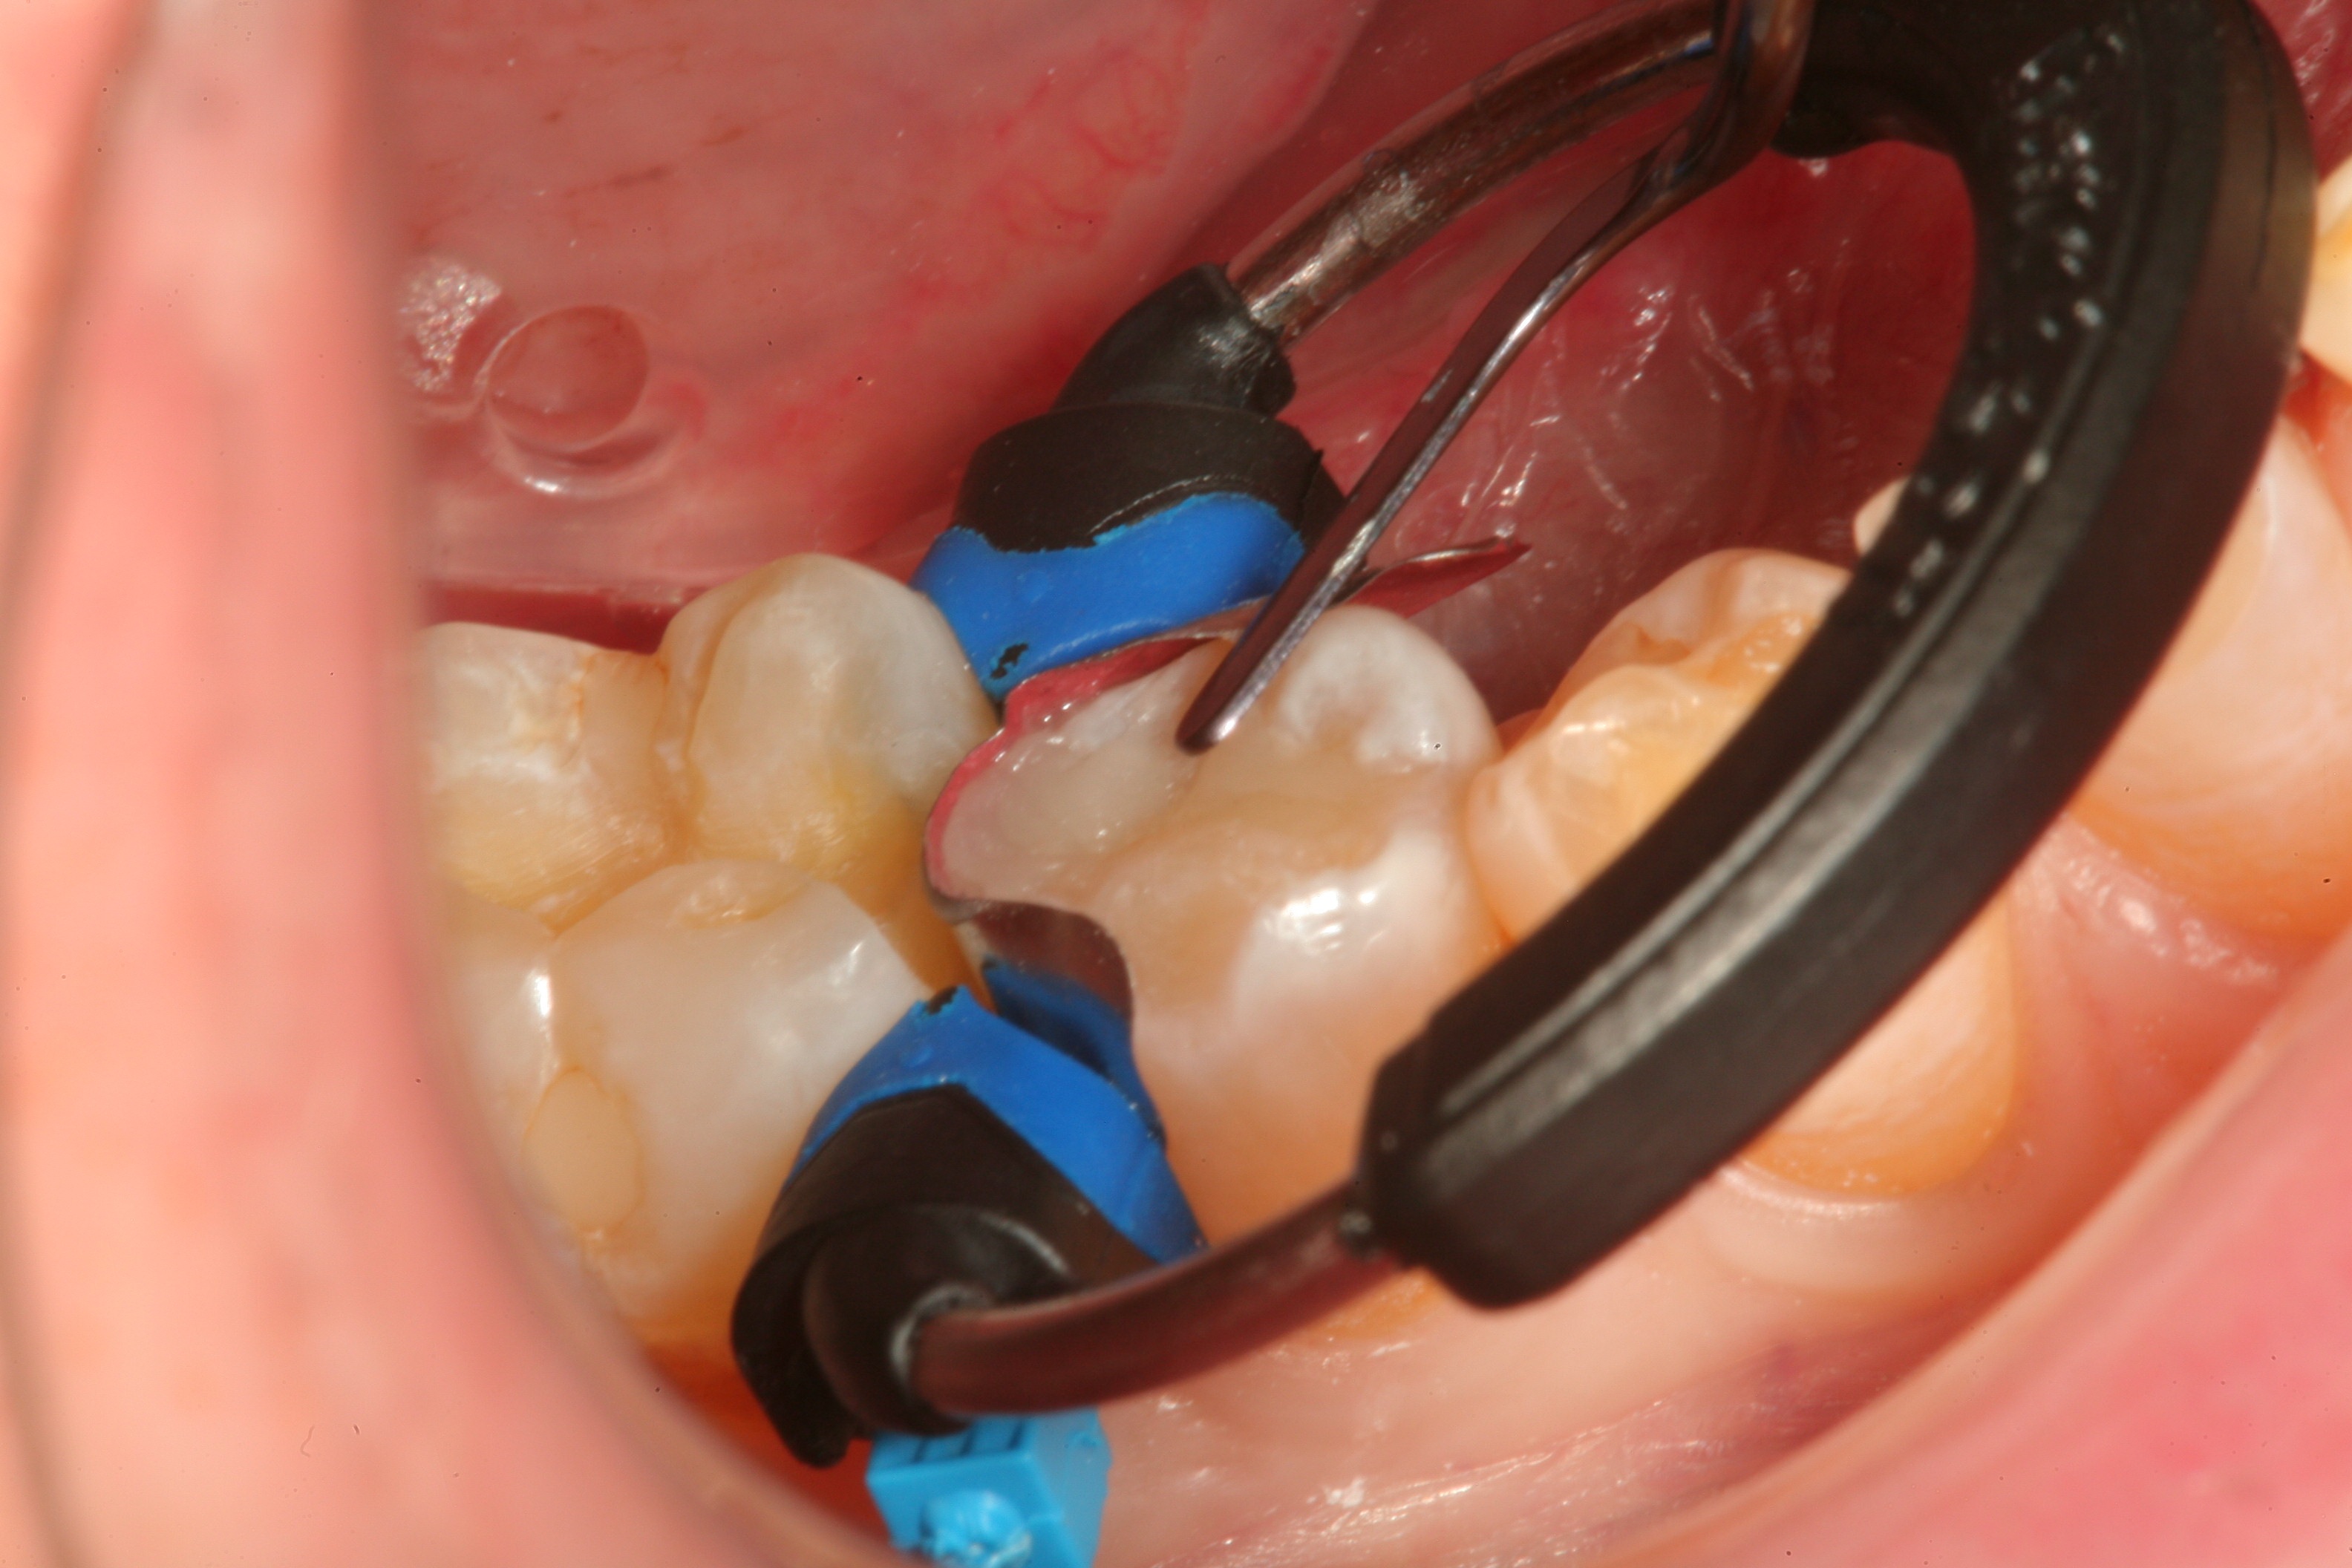

Figure 7

Fig 8. After isolation, a sectional matrix is placed to restore contact and proximal anatomic form to the composite to be placed. The goal is to perform as little rotary finishing and polishing as possible by having the matrix fit precisely to the cavity margins.

Figure 8